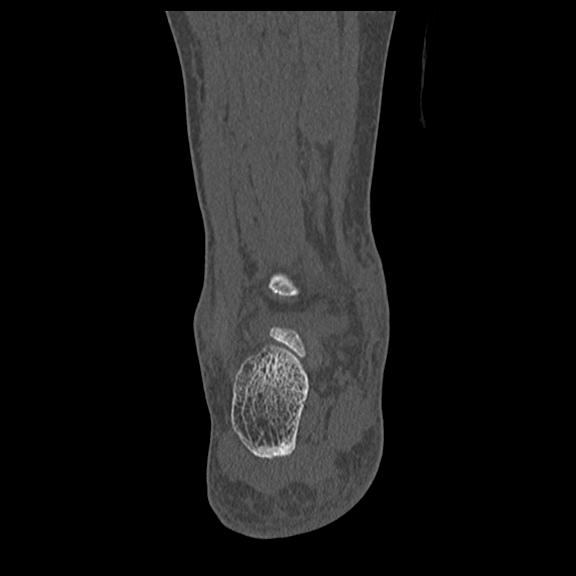

102755 1/4 2R 1/15 2R 右足関節 68歳女性 右三果脱臼骨折